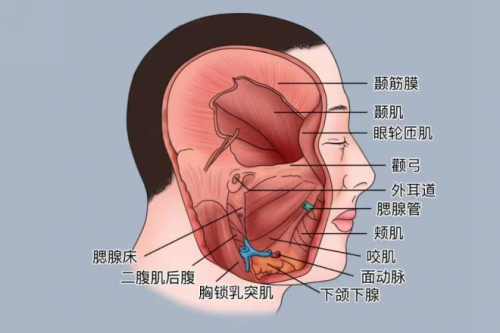

颞骨区域结构复杂,紧邻多个重要神经及血管,手术操作难度较高。如果稍有不慎,可能导致面瘫或听力永久丧失等严重后果。面对风险,娄卫华教授组织团队进行了周密的术前讨论,根据患者年龄、身体状况及病情特点,制定了一套精准且微创的手术方案,既能完整切除肿物,又最大限度保护周围正常组织。